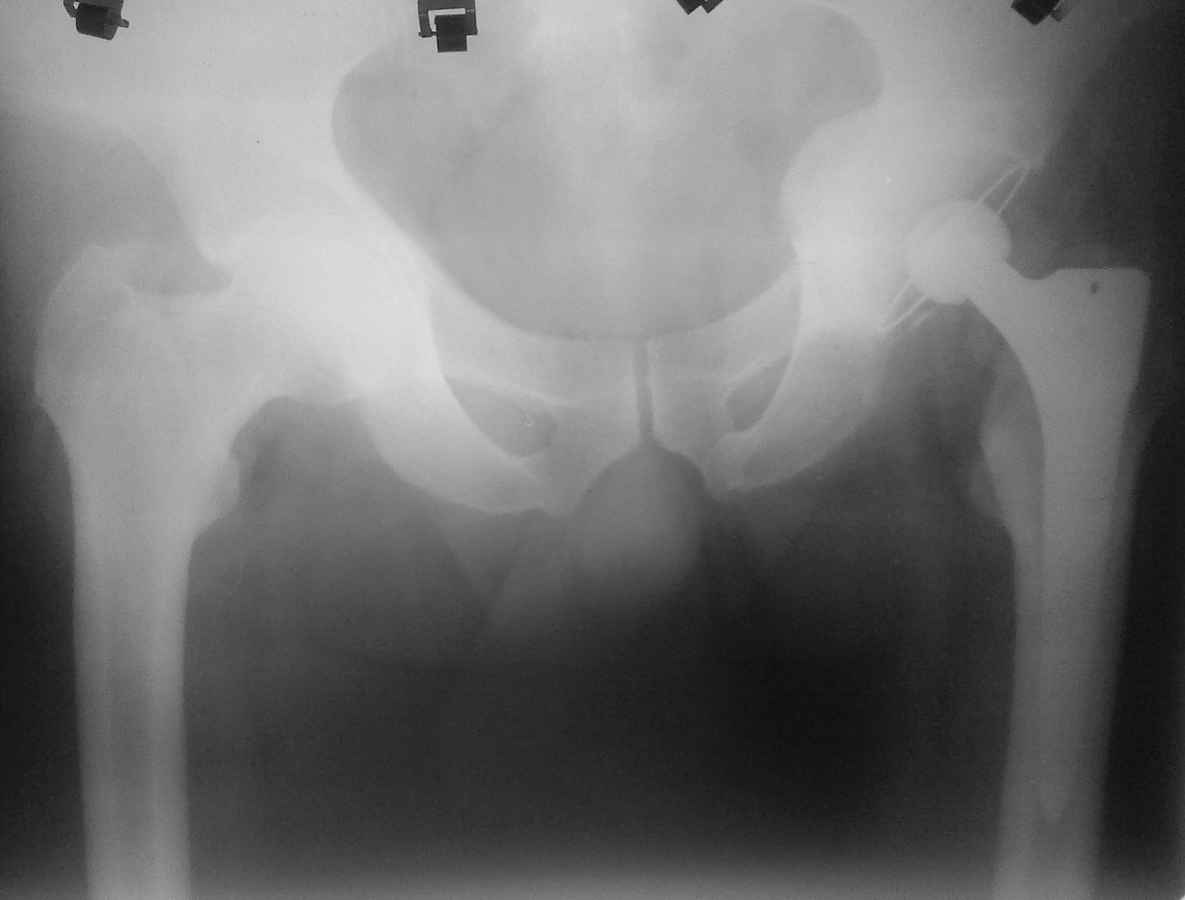

Здравствуйте. Уважаемые коллеги, поделитесь опытом у кого какая тактика при протрузионных коксартрозах

У нас в клинике принято выполнять костную пластику дна стружкой из гололки, а потом цементную чашку (снимки прилагаю). Выскажите свои взгляды на эту проблему, пожалуйста.